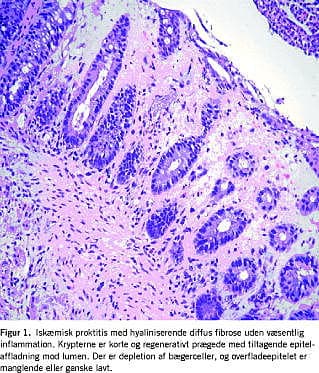

På mistanke om tumor blev der foretaget en magnetisk resonans (MR)-scanning, der afkræftede tumormistanken, men viste ødem perirektalt. Mikroskopisvar viste akut iskæmisk proktitis (Figur 1 ). Ved en sigmoideoskopi ti dage efter indlæggelsen var der spontan remission af tilstanden.